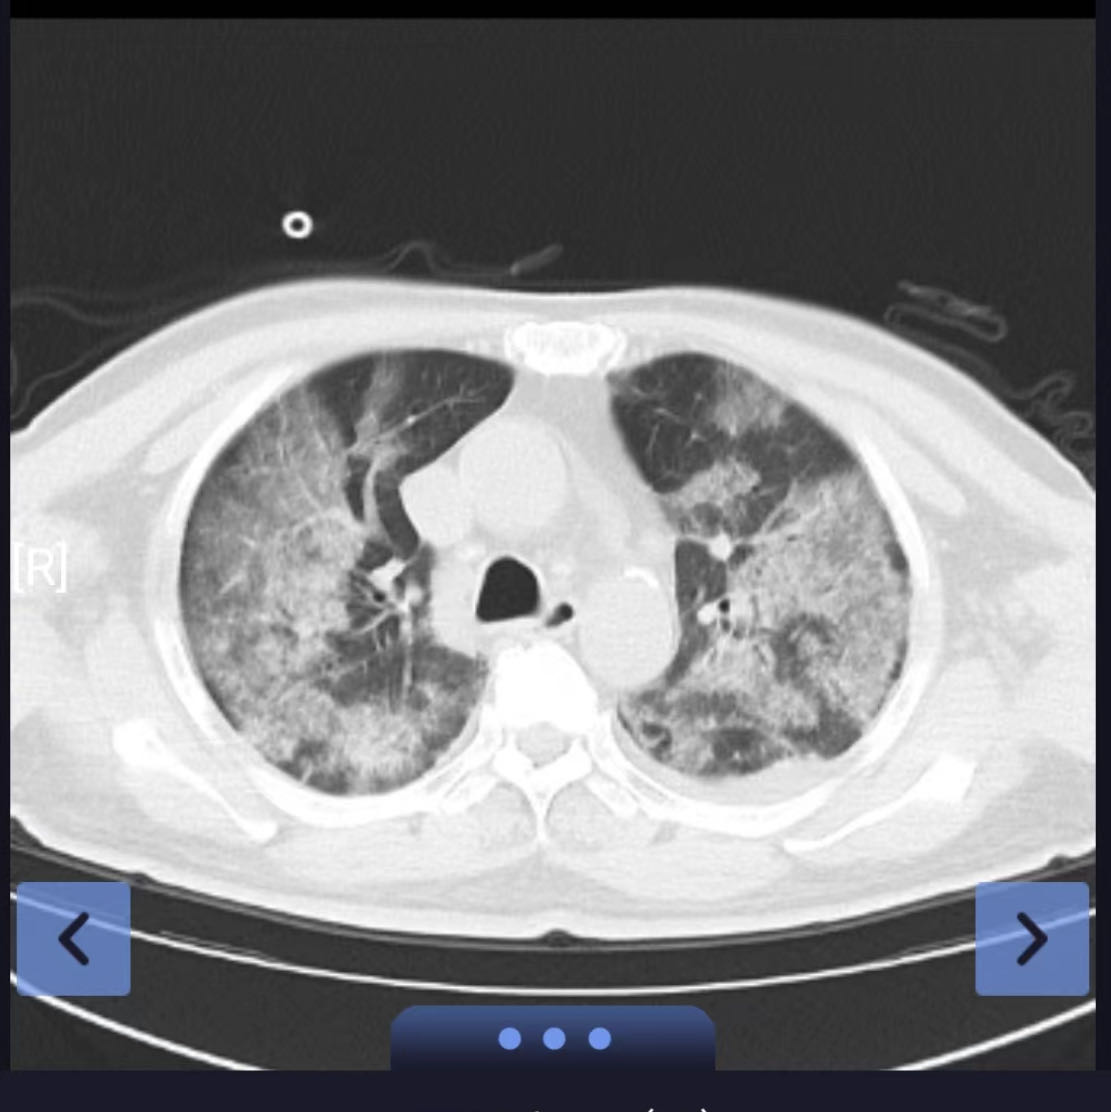

吴某,男,79岁,因发热7天来院就诊,既往有高血压病、糖尿病、冠心病、脑梗塞病史,外院核酸检测阳性,肺部CT提示病毒性肺炎。入院时C-反应蛋白、白介素-6、降钙素原等炎症指标均偏高,入院后给予积极氧疗、抗病毒、抗炎、止咳化痰等对症支持治疗。,患者畏寒发热情况虽有所缓解,但是氧合指数却出现恶化趋势,立即复查肺部CT后显示为“大白肺”。病情急转而下,谢丽华教授立即组织全科医生为该患者进行多学科讨论,调整治疗方案,与家属沟通病情。考虑到患者的年龄,患者对ICU的恐惧心理以及家庭经济情况,采用高流量氧疗+俯卧位通气联合药物治疗,密切关注患者病情变化。

患者虽然氧合差,但好在意识清醒。医护人员多次鼓励疏导,增强其抗击疾病信心,叮嘱其积极进食,增强营养;。高流量吸氧后,患者指脉氧能维持在90%以上,并嘱其每日尽可能长时间俯卧位通气。因患者感染新冠病毒诱发炎症风暴,导致危重型新冠肺炎,及时、准确的诊疗是成功的关键。继续奈玛特韦/利托那韦抗病毒治疗、加大甲泼尼龙治疗剂量,同时考虑到炎症风暴导致DIC、血液高凝,给予低分子肝素抗凝。经过以上综合治疗后,患者症状明显缓解,各项化验指标好转,指脉氧饱和度维持在96%以上,最终在治疗后5天停用高流量氧疗,改为鼻导管吸氧。治疗后第七天复查肺部CT,“大白肺”已得到充分逆转,患者也露出了久违的笑容。

前后肺部CT对照(相隔7天)